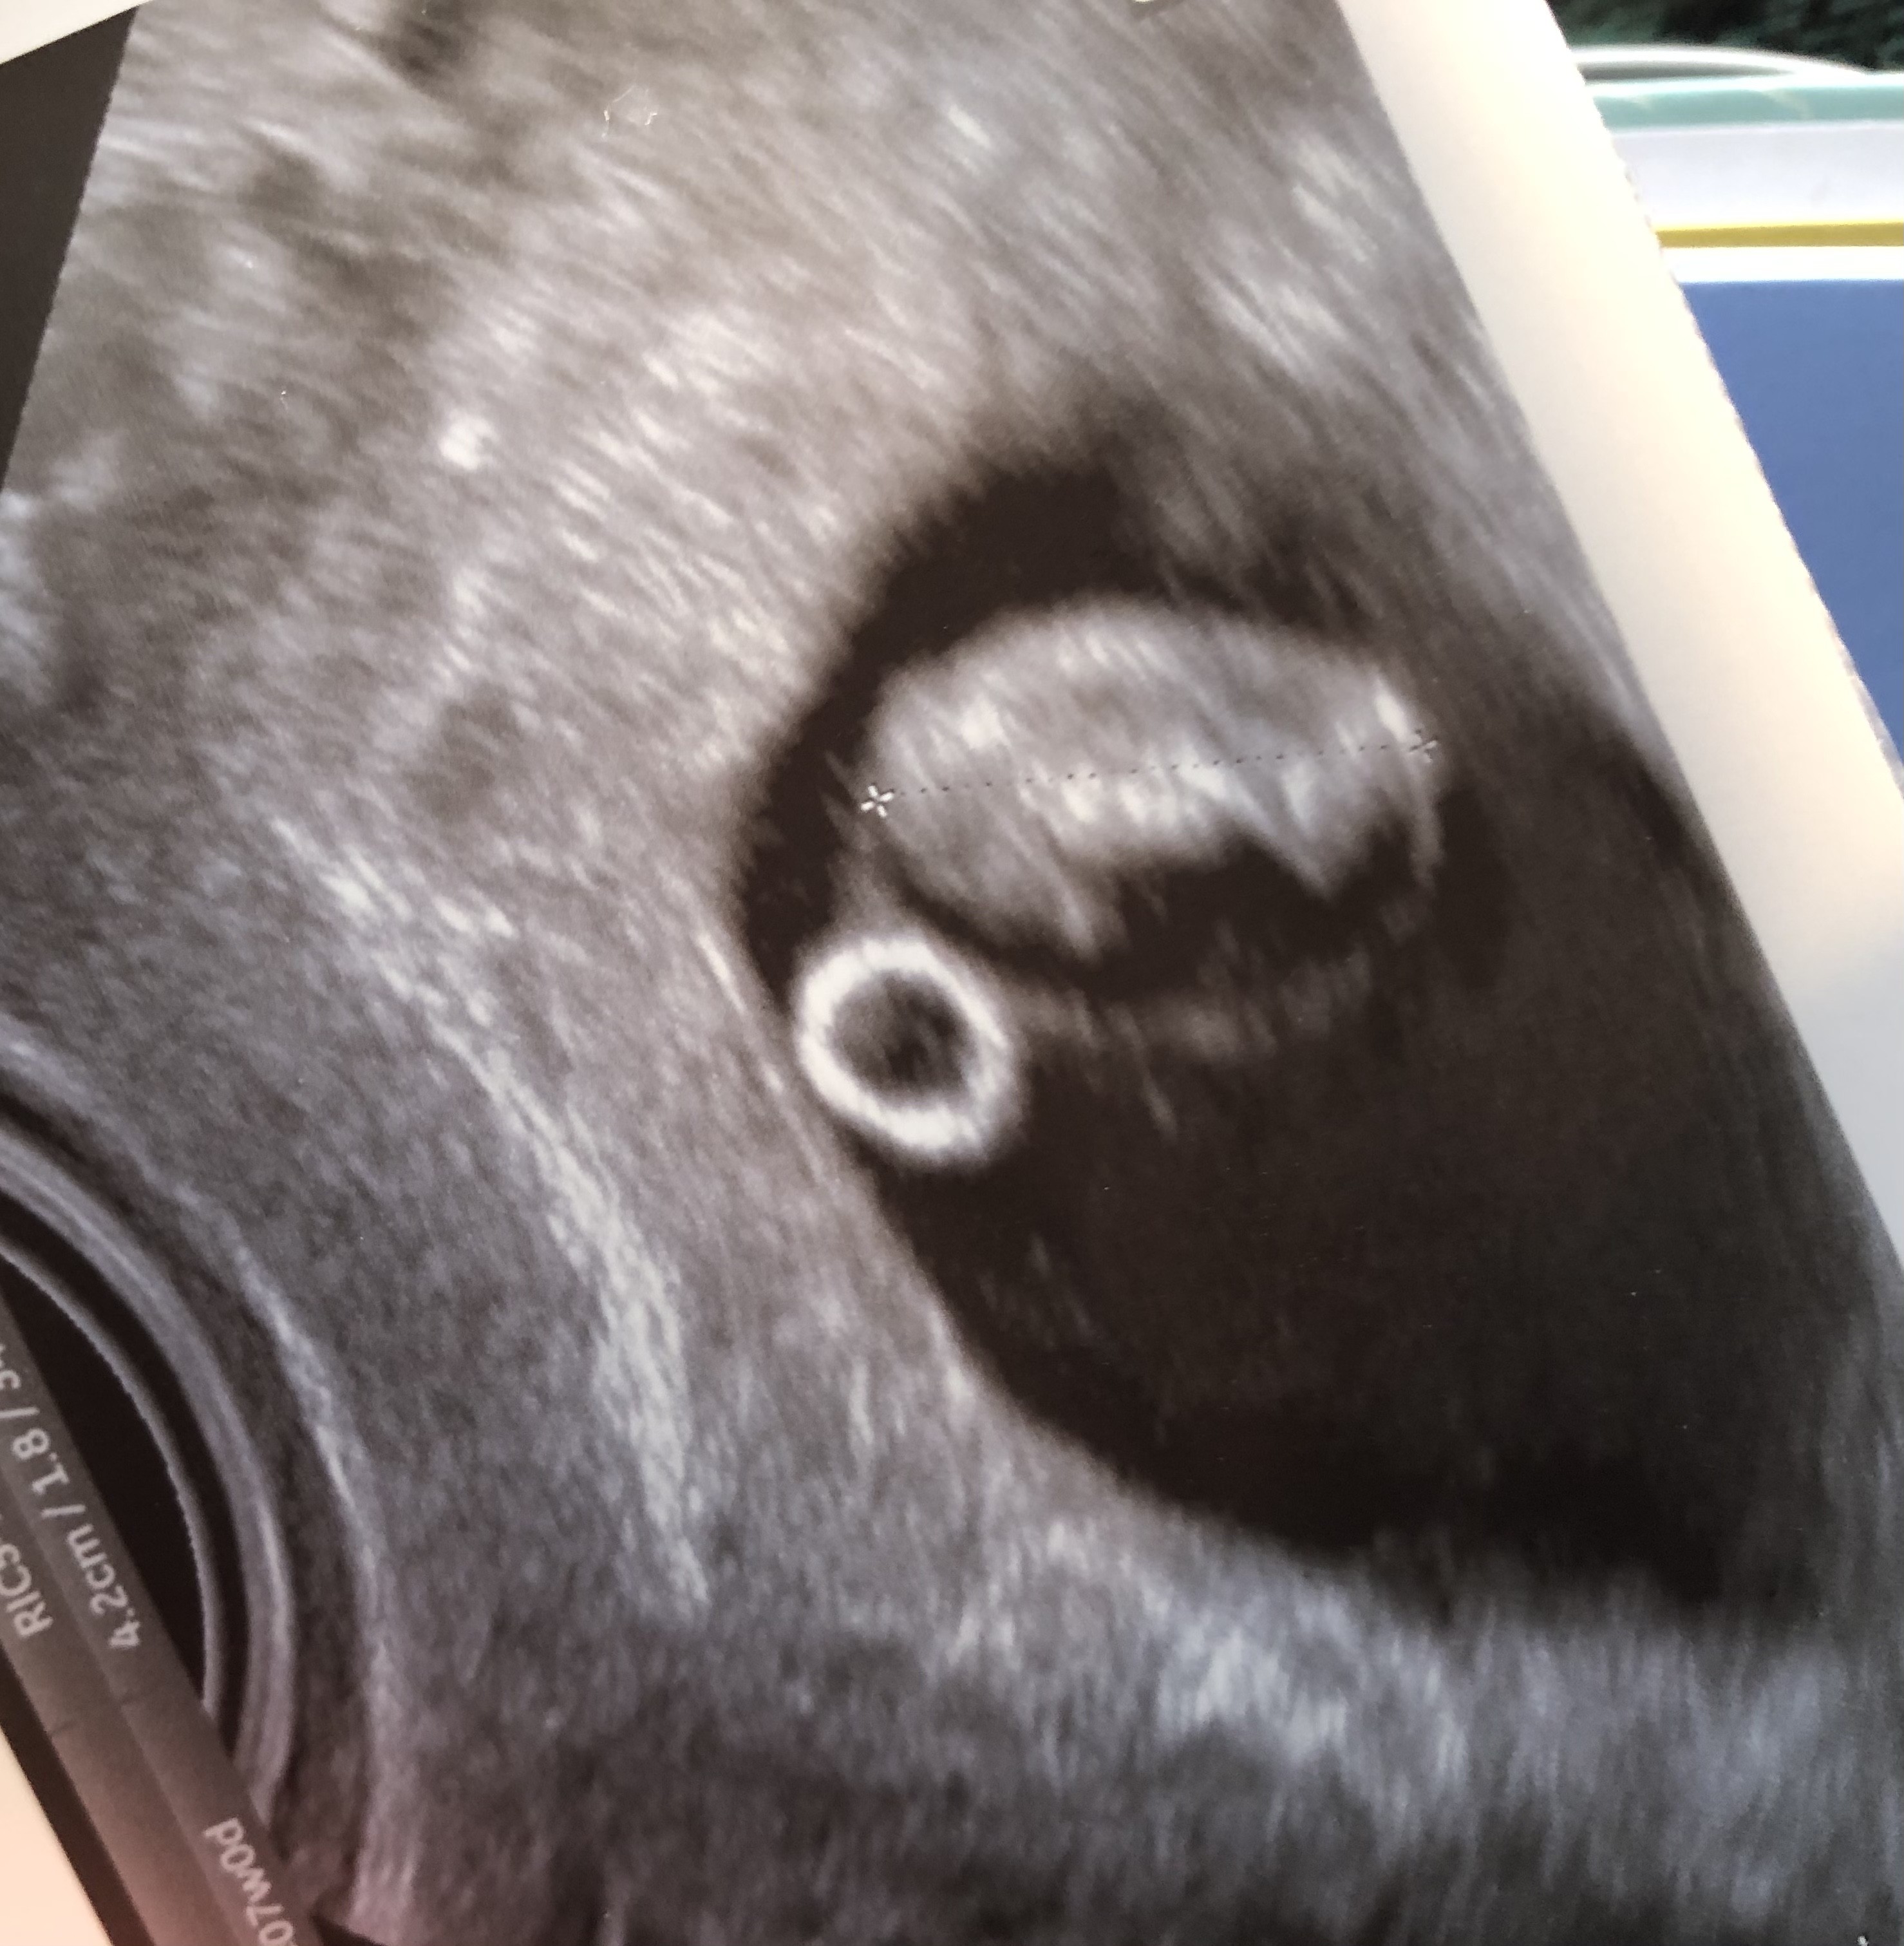

Ja dzisiaj po wizycie 8w5d, na USG udało mi się nawet zobaczyć jak dzidzia porusza łapkami 😍😍😍 umówiona na usg prenatalne 1szego trymestru na 11+4. Jutro rano dopiero robię full pakiet badań z krwi. Doktor na moją odpowiedź o dolegliwości również podsumowała że super ze są 😂 Dzisiaj się właśnie od rana zastanawiam dlaczego za każdym razem jak ktoś kto wie lub dowiaduje się że jestem w ciąży pyta jak się czuję, ja odpowiadam "dobrze" a dopiero potem mówię no mam mdłości, wymiotuję rano, wymiotuję czasem wieczorem od niedawna, zaparcia, wzdęcia, kolki.zmeczenie....."ale ogólnie dobrze się czuję" haha zamiast powiedzieć że w sumie czasem średnio albo kiepsko 😂

Załączniki

• IMG_20210309_155150.jpg

IMG_20210309_155150.jpg

289,6 KB · Wyświetleń: 90